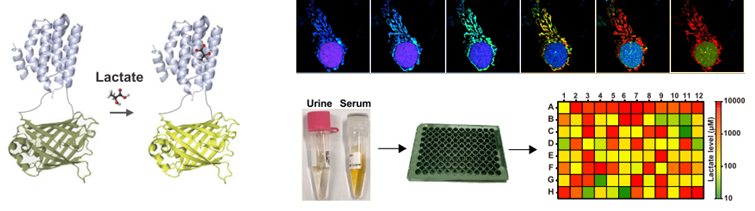

乳酸是重要的能量燃料、合成砌块和信号分子,是具有多种关键作用的代谢“明星”,在生理和病理过程中发挥重要作用。乳酸代谢呈现剧烈的动态变化和复杂的空间分布,传统的生化方法难以实现活细胞和在体水平的动态追踪。我们发明了高特异、高响应、超灵敏的乳酸荧光探针FiLa,绘制了亚细胞乳酸代谢图谱,本研究意外发现线粒体基质内富集了高浓度乳酸,解决了该领域争议了几十年的重要科学问题。建立了基于FiLa探针的临床体液样本即时检测技术,发现尿液乳酸显著升高可能作为母系遗传性糖尿病伴耳聋(MIDD)疾病的潜在筛查标志物,为临床诊断提供了重要依据。(Cell Metabolism 2023, 35, 220; Nature Protocols 2023, in press)